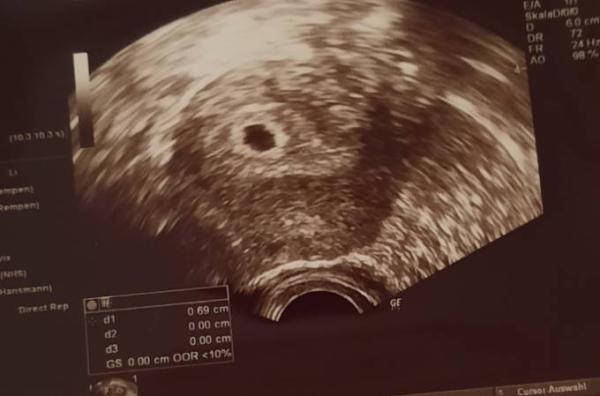

Hallo ihr lieben, sah das bei jemanden auch in der Woche so aus? Es ist kein Dottersack zu sehen & auch kein Embryo habe Angst das es eine Eileiterschwangerschaft ist.

Hallo, Es ist ja eine Fruchthöhle in der Gebärmutter, also wird es keine Eileiterschwangerschaft sein. Dottersack und embryo sollten eine Woche später jedenfalls zu erkennen sein. Liebe Grüße

Mach dir keine Sorgen! Wenn eine deutliche Fruchthöhle in der Gebärmutter zu sehen ist, ist es in der Regel keine Eileiterschwangerschaft.

Alle Schwangerschaften sind unterschiedlich. War bei meiner ersten Schwangerschaft 6+3 beim ersten Ultraschall da sah man Embryo + Herzschlag . Bei der jetzigen Schwangerschaft 6+4 nur eine fruchthöhle, bitte nicht mit anderen Schwangerschaften vergleichen alle sind individuell lg